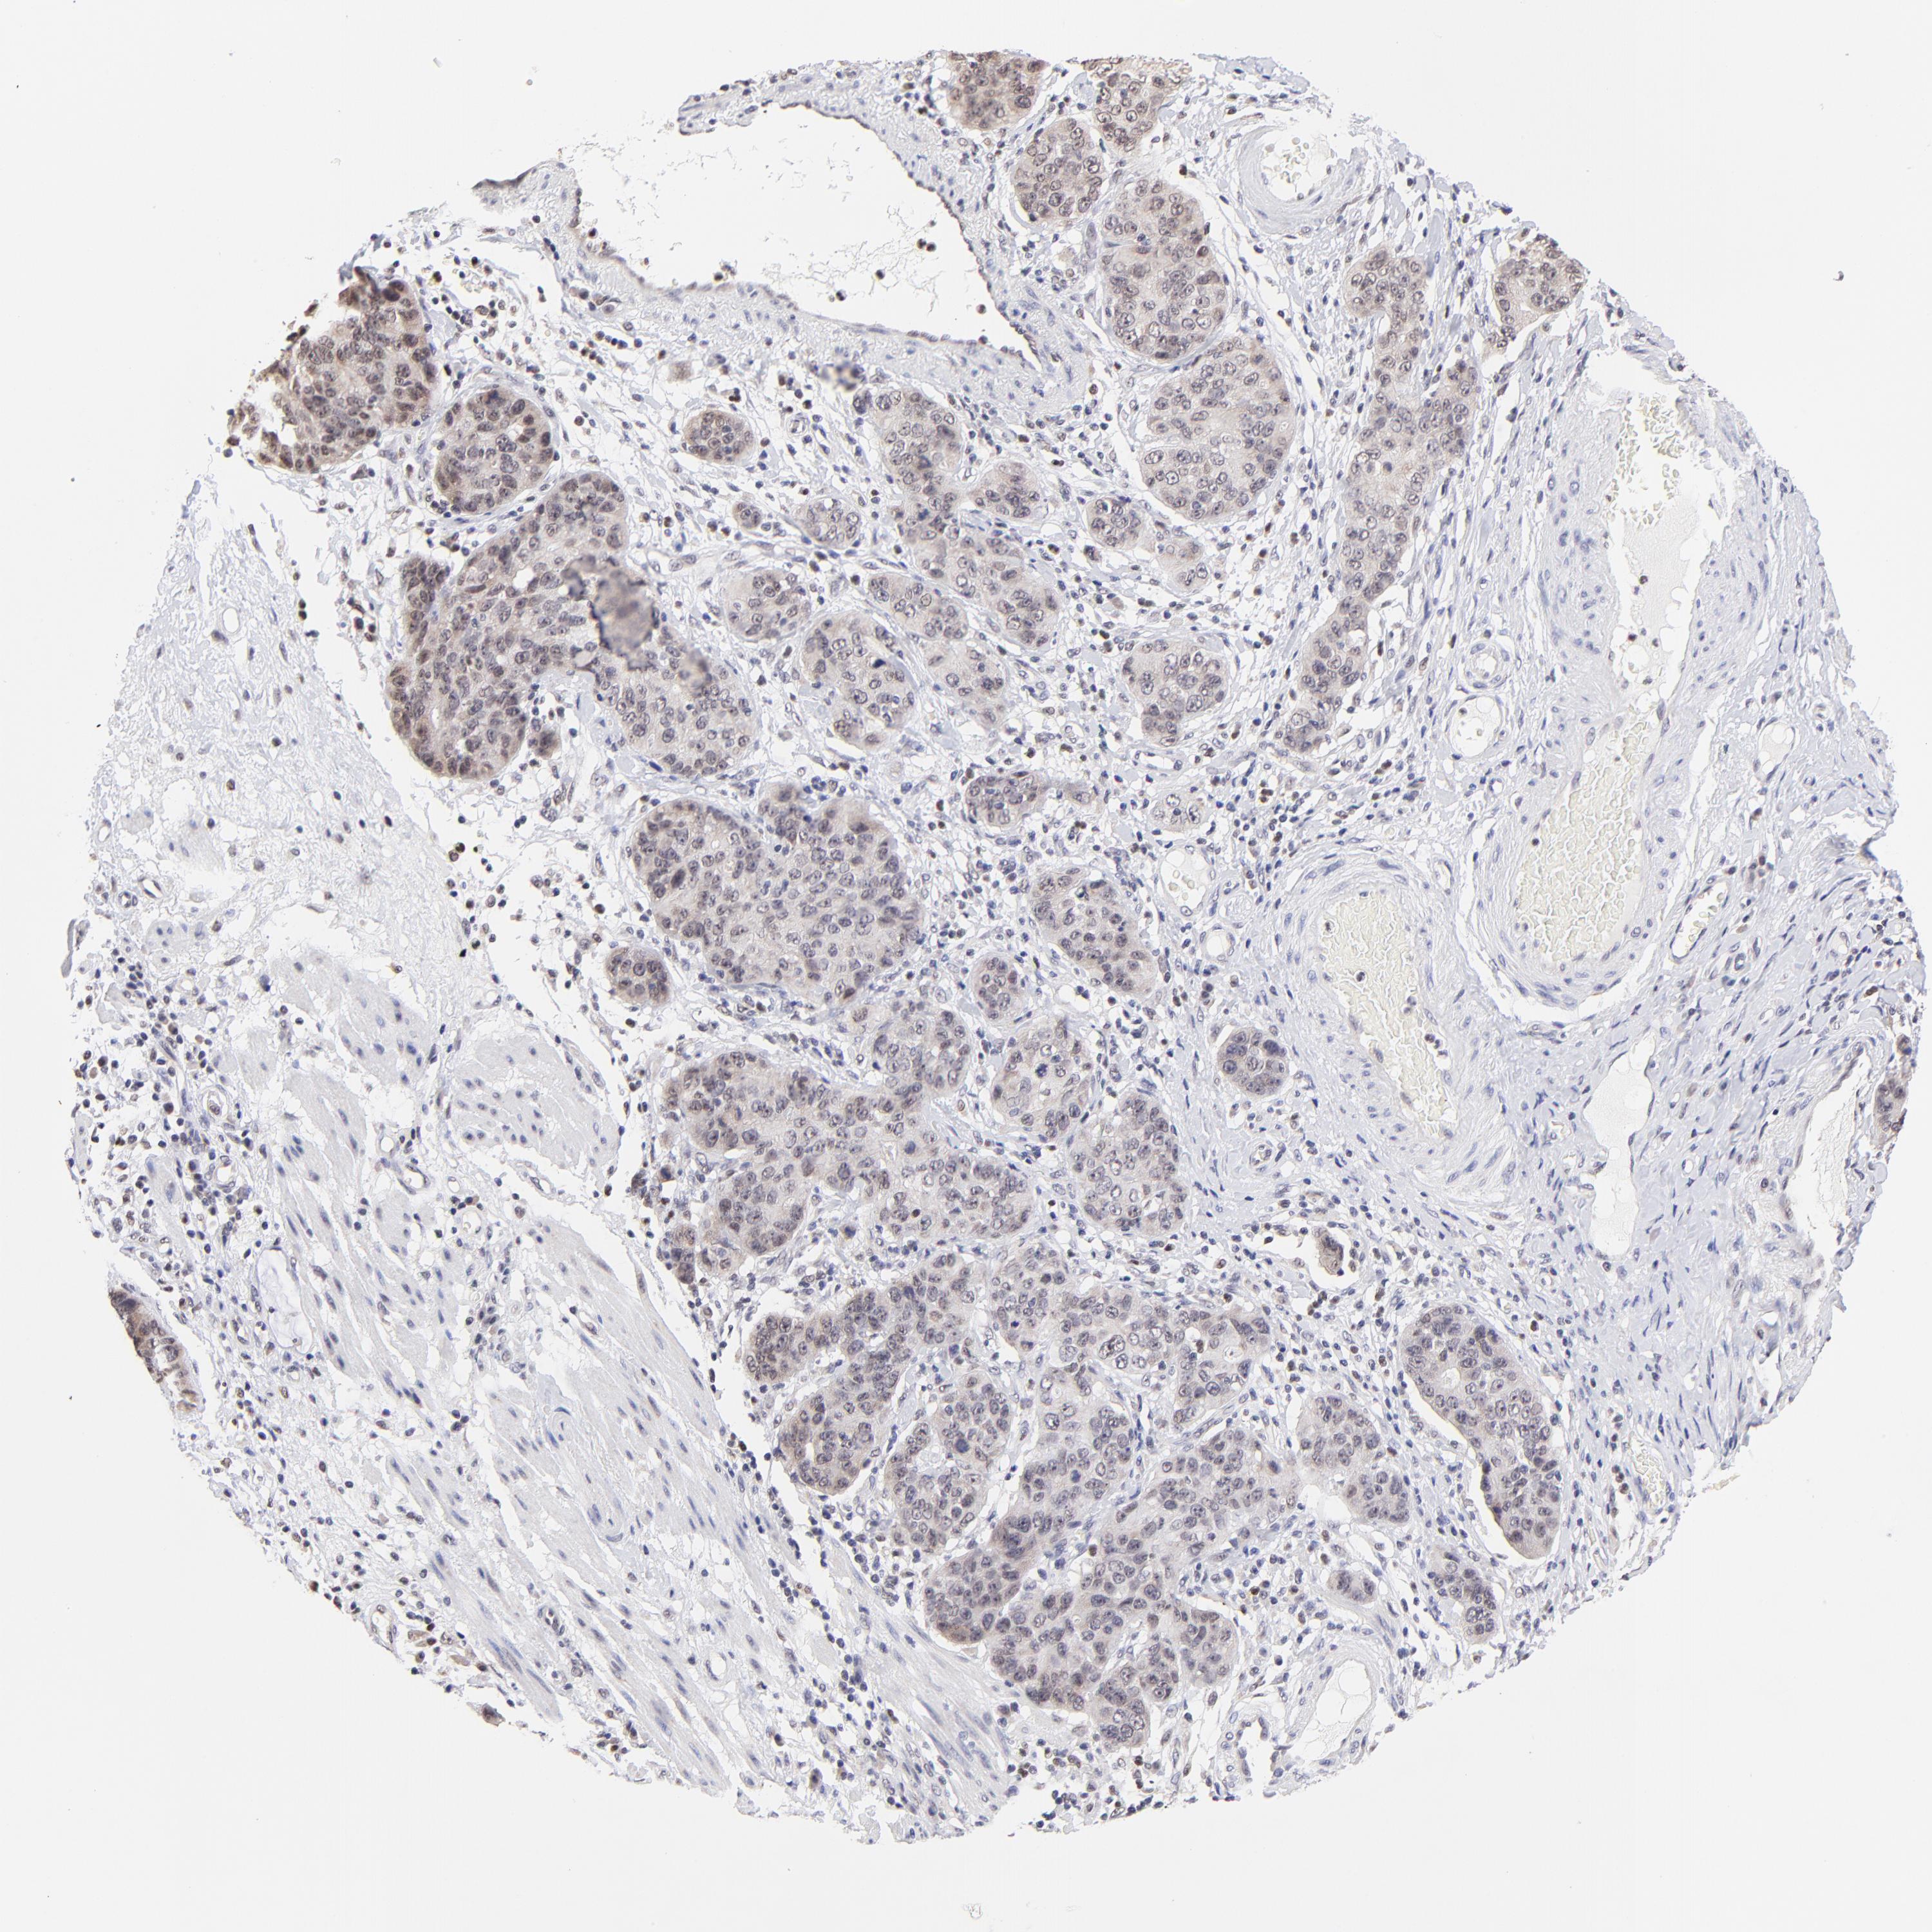

STOMACH CANCER - Protein expressioni

A mouse-over function shows sample information and annotation data. Click on an image to view it in a full screen mode. Samples can be filtered based on level of antibody staining by selecting one or several of the following categories: high, medium, low and not detected. The assay and annotation is described here.

Note that samples used for immunohistochemistry by the Human Protein Atlas do not correspond to samples in the TCGA dataset.

Antibody stainingi

Antibody staining in the annotated cell types in the current human tissue is reported as not detected, low, medium, or high, based on conventional immunohistochemistry profiling in selected tissues. This score is based on the combination of the staining intensity and fraction of stained cells.

Each image is clickable and will lead to virtual microscopy that enables deeper exploration of all samples and also displays staining intensity scores, fraction scores and subcellular localization as well as patient and tissue information for each sample.

Antibody HPA003142

Staining

High

Medium

Low

Not detected

Intensity

Strong

Moderate

Weak

Negative

Quantity

>75%

75%-25%

<25%

None

Location

Nuclear

Cytoplasmic/membranous

Cytoplasmic/membranous,nuclear

Adenocarcinoma, NOS